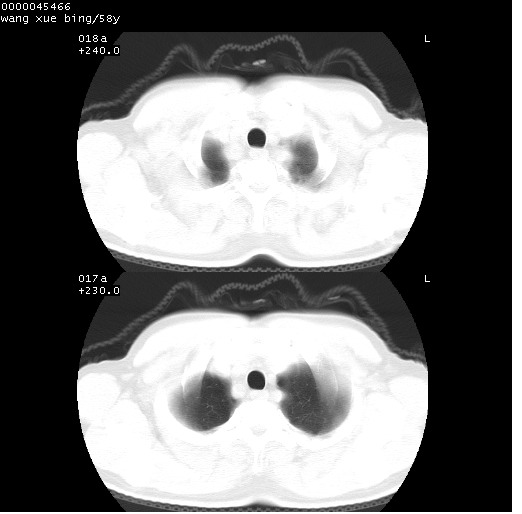

患者 男,58岁。咳嗽、咯血3月余。

胸部cr x线片提示:1)右下肺脓肿。2)右下肺周围型肺癌不排除。建议:行ct扫描检查。

胸部ct轴位平扫(层厚10mm,螺距1.5,重建间隔10mm),图像如下:

右肺下叶团块及不规则空洞,内壁不规则,外缘见粗长毛刺,临近胸膜明显增厚并与病灶关系密切。支持考虑:右肺肺脓肿!建议穿刺病理检查待除外周围型肺癌!

右肺下叶见不规则厚壁空洞,内壁不规则,外缘见粗长毛刺,临近胸膜明显增厚并与病灶关系密切。支持考虑:周围型肺癌!

右肺下叶周围型肺癌伴空洞形成!征象比较明显!分叶、毛刺、胸膜凹陷征、厚壁空洞,壁结节!

空洞壁厚,不规则,其内可见壁结节,周围可见毛刺及阻塞性炎变,多考虑癌性病变.